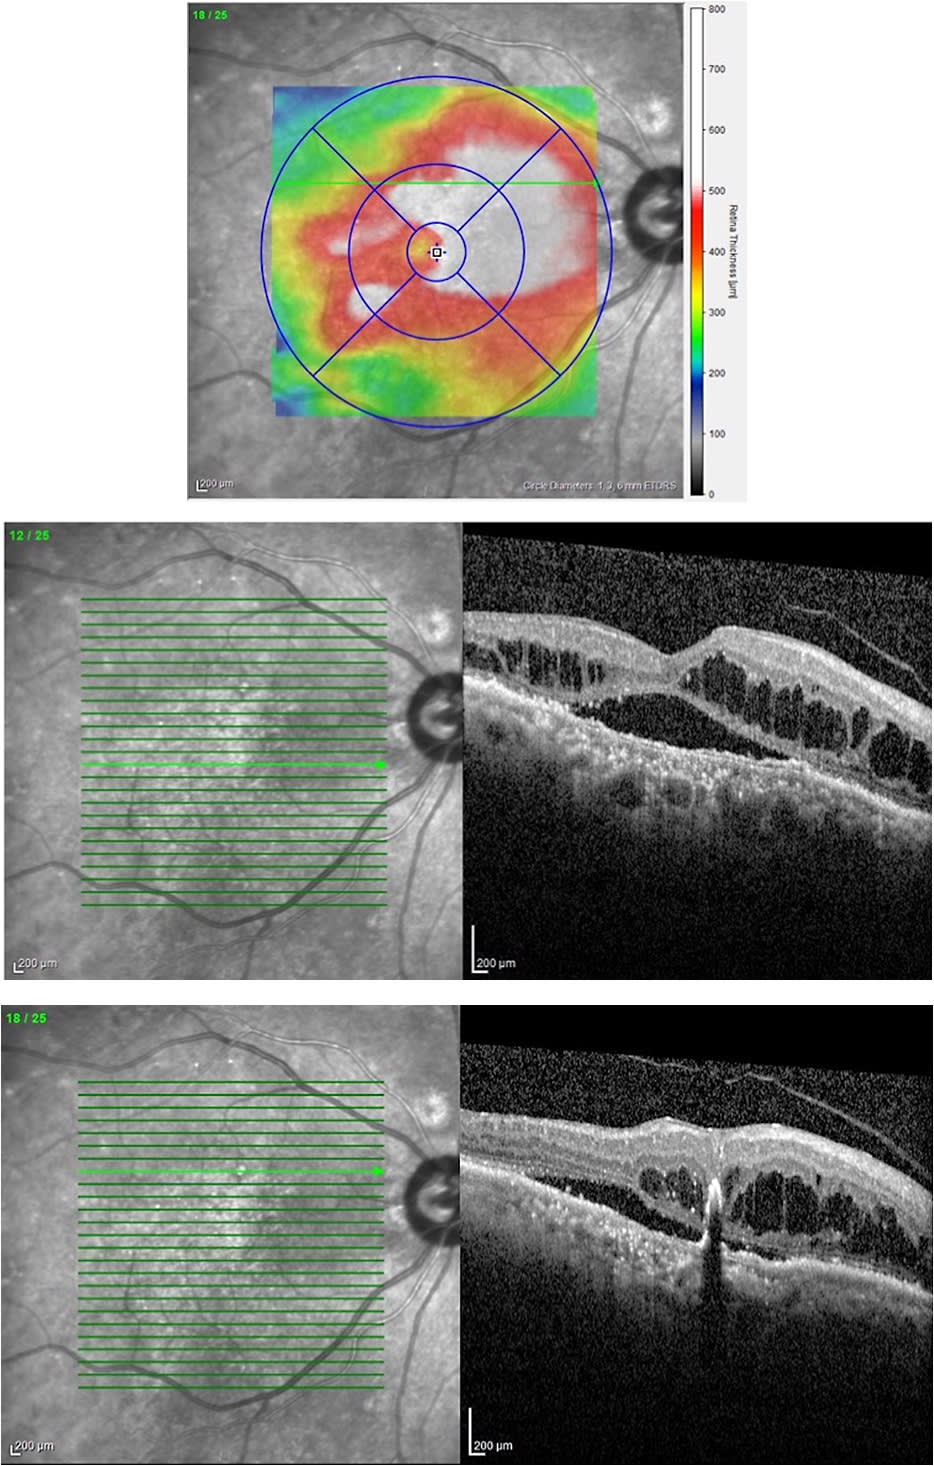

Although 9 consecutive injections did not improve the edema, the application of microsecond pulsing laser along with 3 additional anti-VEGF injections was able to significantly improve the edema at 11 months of follow-up. The vision of the patient improved from 20/100 to 20/80 (Figure 3).

Parameters and treatment locations were documented using the Navilas reporting functionality. After one microsecond pulsing laser treatment, the subretinal fluid and edema significantly improved over a 4-month period. The vision of the patient improved from 20/200 to 20/140 (Figure 6).